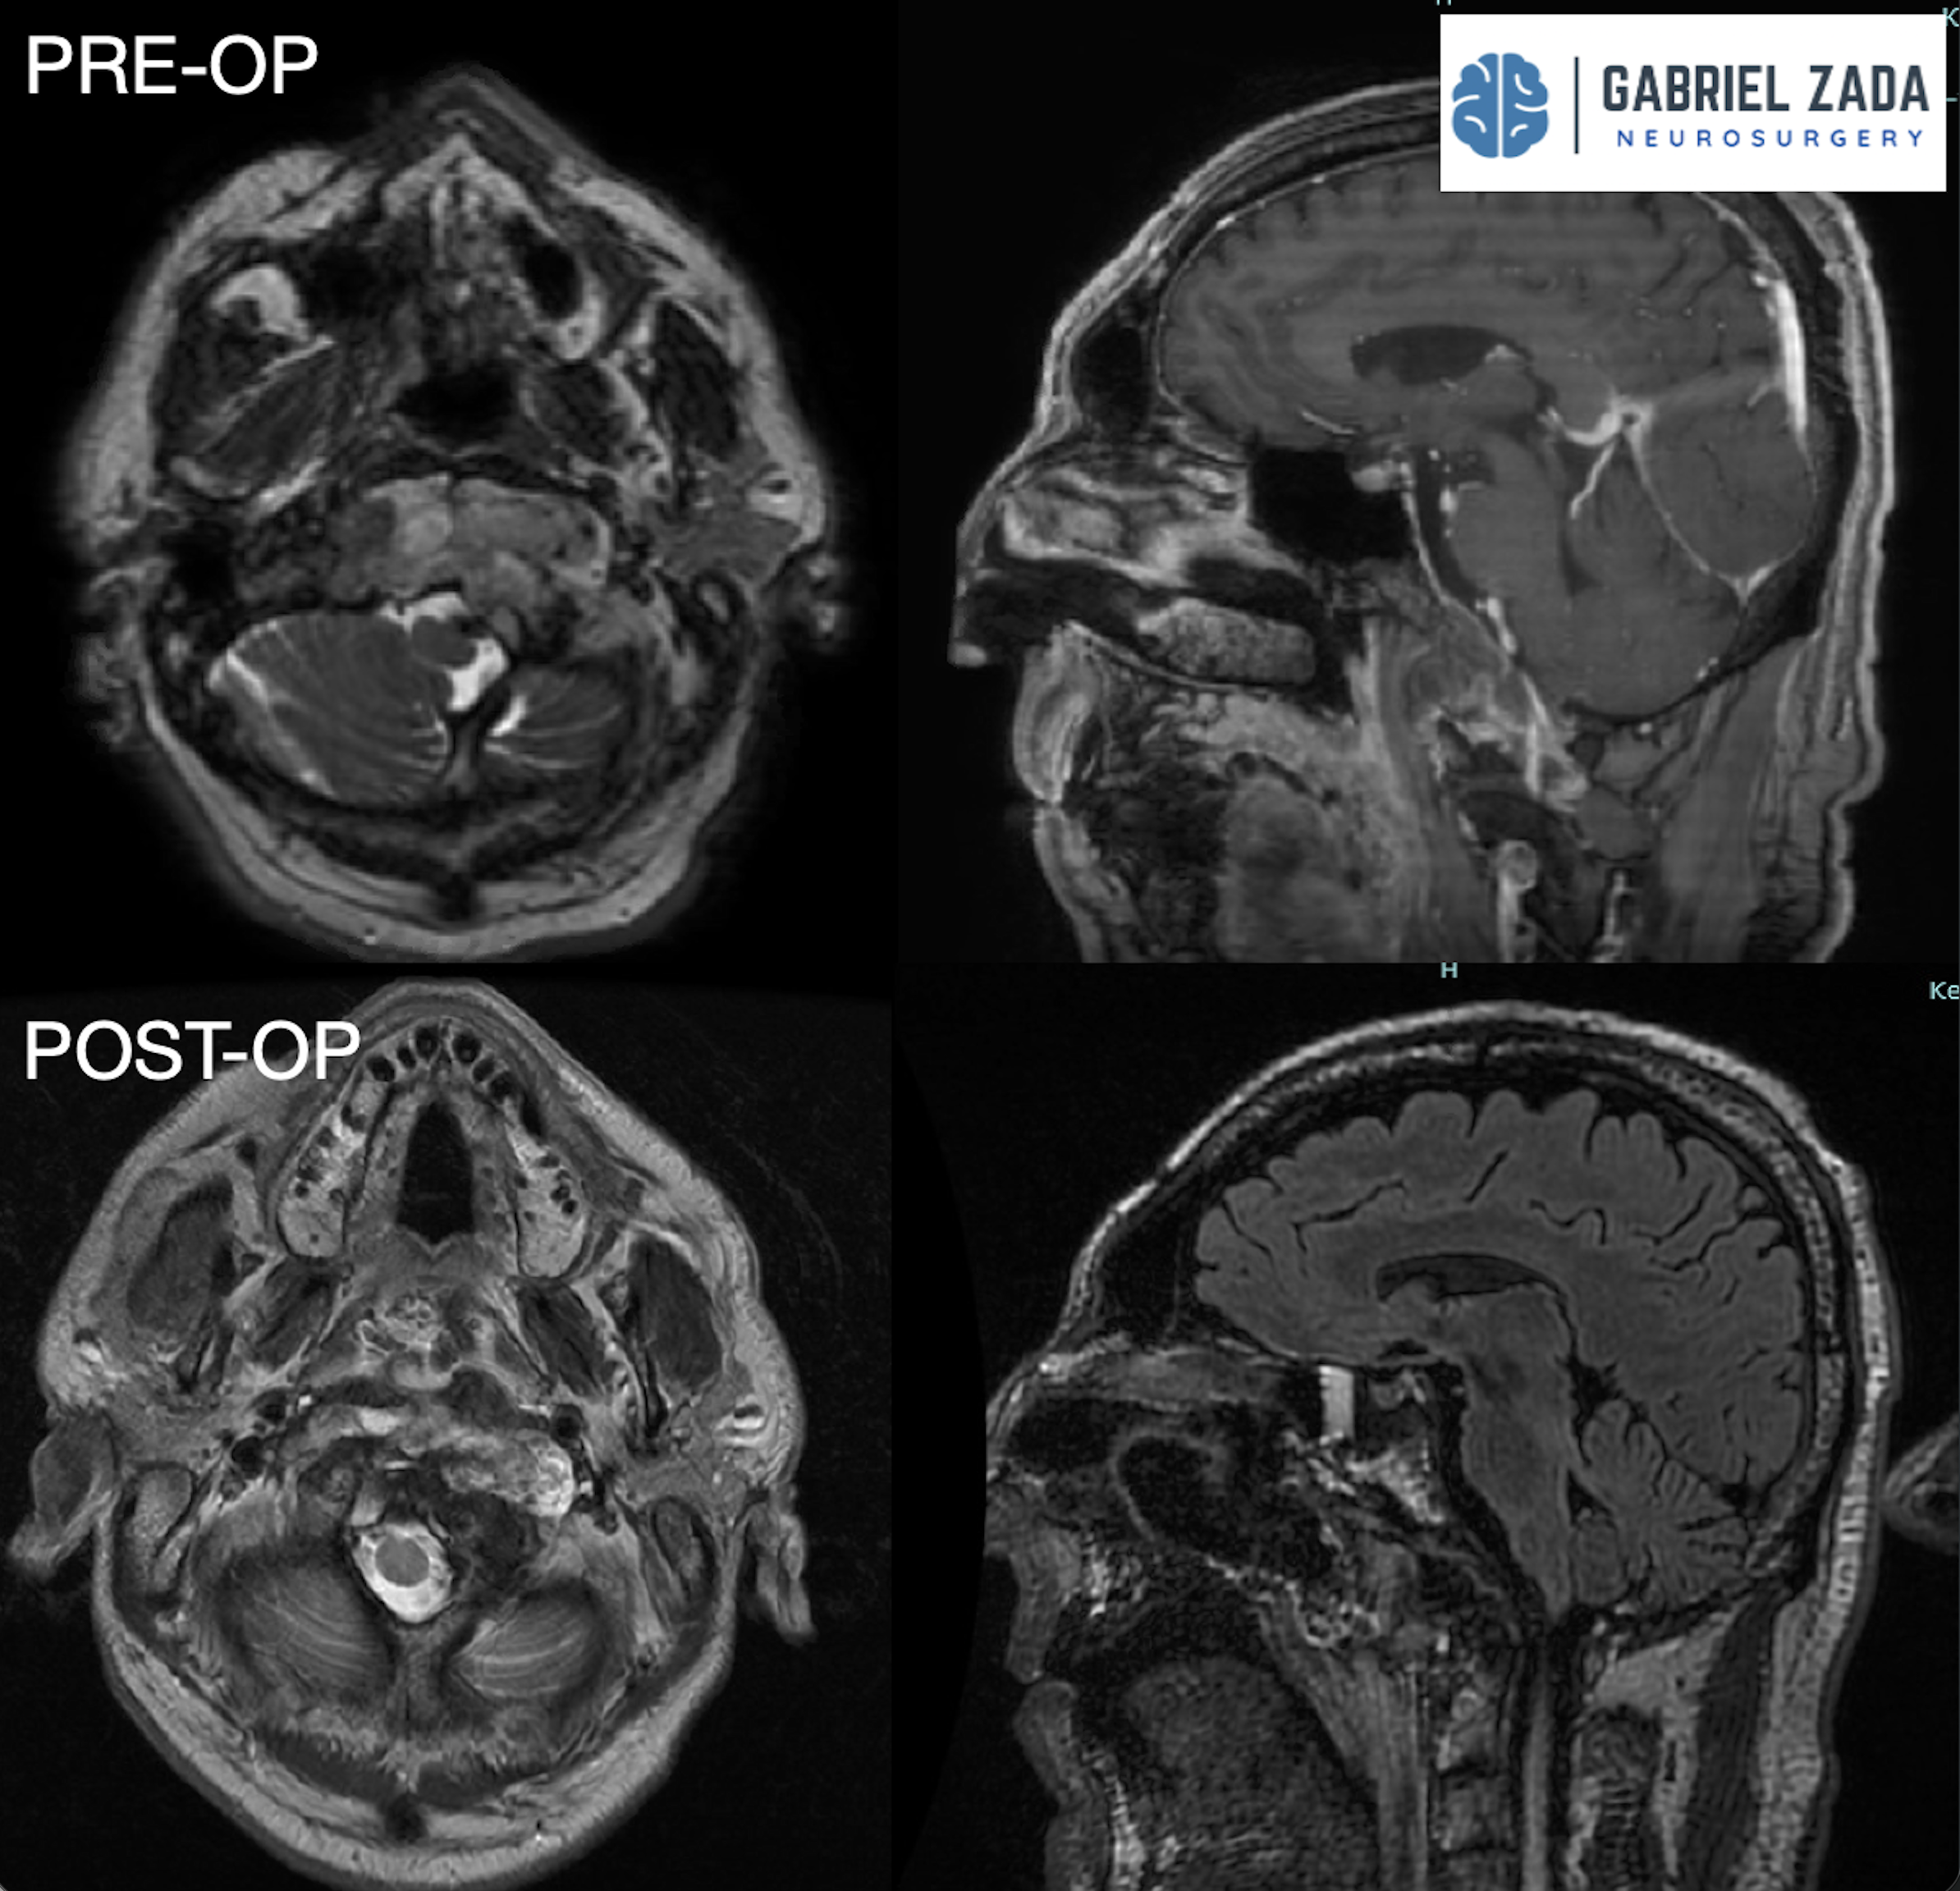

Explore this comprehensive gallery featuring pre‑ and post‑operative imaging of patients with skull‑base tumors treated by Gabriel Zada, MD, MS, FAANS, FACS. These cases highlight Dr. Zada’s expertise in advanced neurosurgical techniques and outcomes.

*Representative cases shown for educational purposes. All images de-identified. Individual results vary.